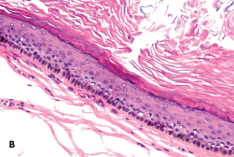

Alexander K.C. Leung, MD, MBBS, FRCPC, FRCP; Alex H.C. Wong, MD

Most benign cutaneous tumors and growths in adolescents are asymptomatic and treatment is for cosmetic reasons. Further evaluation for an underlying disorder is required in some instances, such as in...

epidermal nevi

Kirk Barber, MD, FRCPC